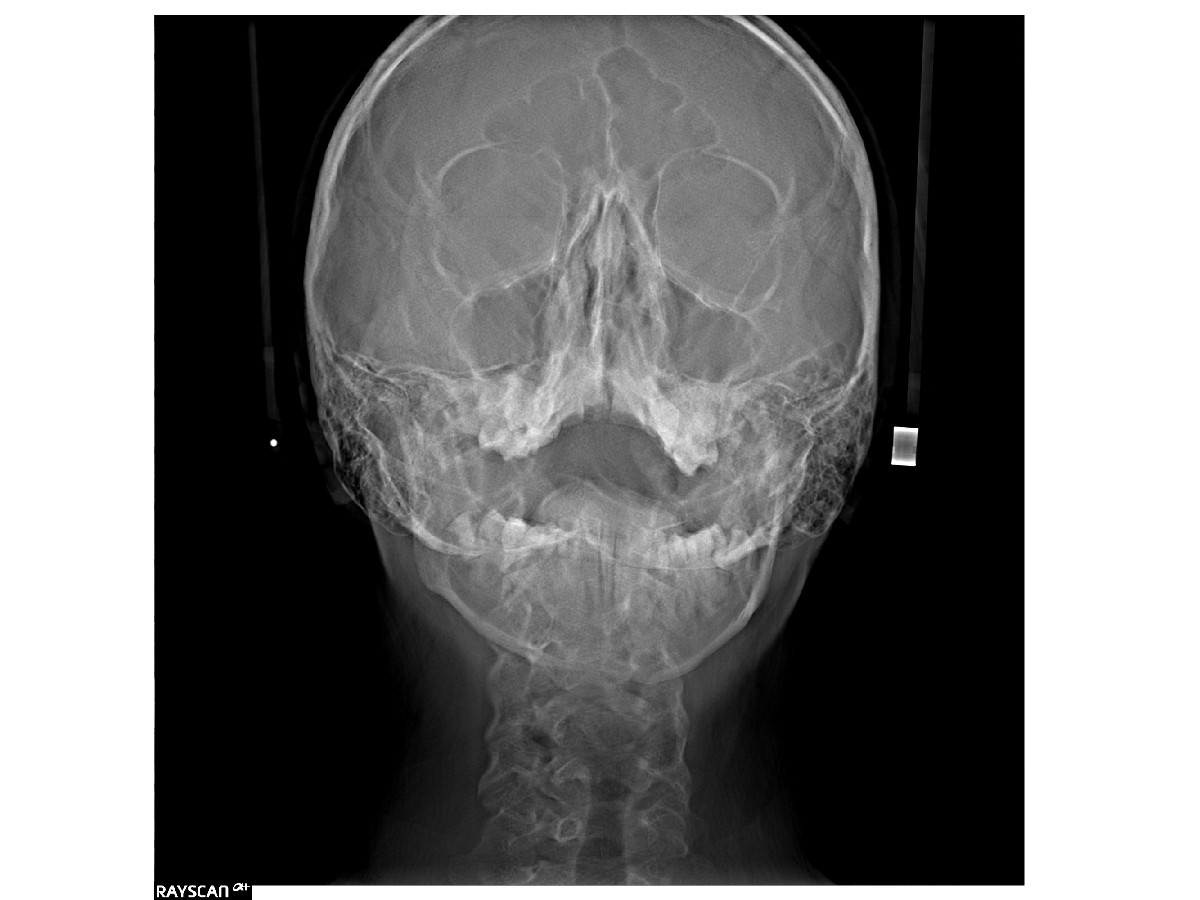

RTG zatok to obrazowe badanie diagnostyczne, które pozwala ocenić kompleksowo stan jam zatokowych. Wykorzystuje niewielką dawkę promieniowania rentgenowskiego do uwidocznienia ewentualnych zmian, takich jak stany zapalne, torbiele, polipy czy deformacje anatomiczne. Dzięki temu można szybko wykryć przyczyny przewlekłego bólu głowy, niedrożności nosa, czy nawracających infekcji i wdrożyć odpowiednie leczenie.

Precyzyjna diagnostyka zaczyna się od dokładnego obrazu. RTG zatok pozwala wykryć stany zapalne, torbiele oraz inne nieprawidłowości wpływające na swobodne oddychanie i codzienny komfort. W ESDENT Wrocław wykorzystujemy nowoczesny sprzęt, zapewniając wyraźne zdjęcia przy minimalnej dawce promieniowania. Umów się na badanie i zadbaj o zdrowie zatok – bez zbędnego czekania i z gwarancją profesjonalnej, przyjaznej obsługi.

RTG zatok jest stosowane w diagnostyce różnorodnych schorzeń. Pozwala wykryć stany zapalne, torbiele, polipy oraz inne nieprawidłowości, które mogą powodować przewlekłe objawy, takie jak ból głowy, uczucie zatkanego nosa, czy częste infekcje. Obraz rentgenowski dostarcza precyzyjnych informacji, niezbędnych do oceny kondycji zatok i wyboru odpowiedniej metody leczenia zarówno w przypadku leczenia zachowawczego, jak i planowania zabiegów.

Zdjęcie rentgenowskie zatok pozwala na dokładne przygotowanie do operacji, w tym korekcji wad zgryzu. Jest także istotnym narzędziem w analizie wzrostu kości twarzoczaszki, co ma znaczenie zwłaszcza w ortodoncji dziecięcej i młodzieżowej. Wykonanie badania zaleca się przed zabiegami chirurgicznymi w tej okolicy, a także po zakończeniu leczenia, aby ocenić jego skuteczność. Może być również konieczne w przypadkach, gdy standardowa diagnostyka laryngologiczna nie przynosi jednoznacznych wyników.